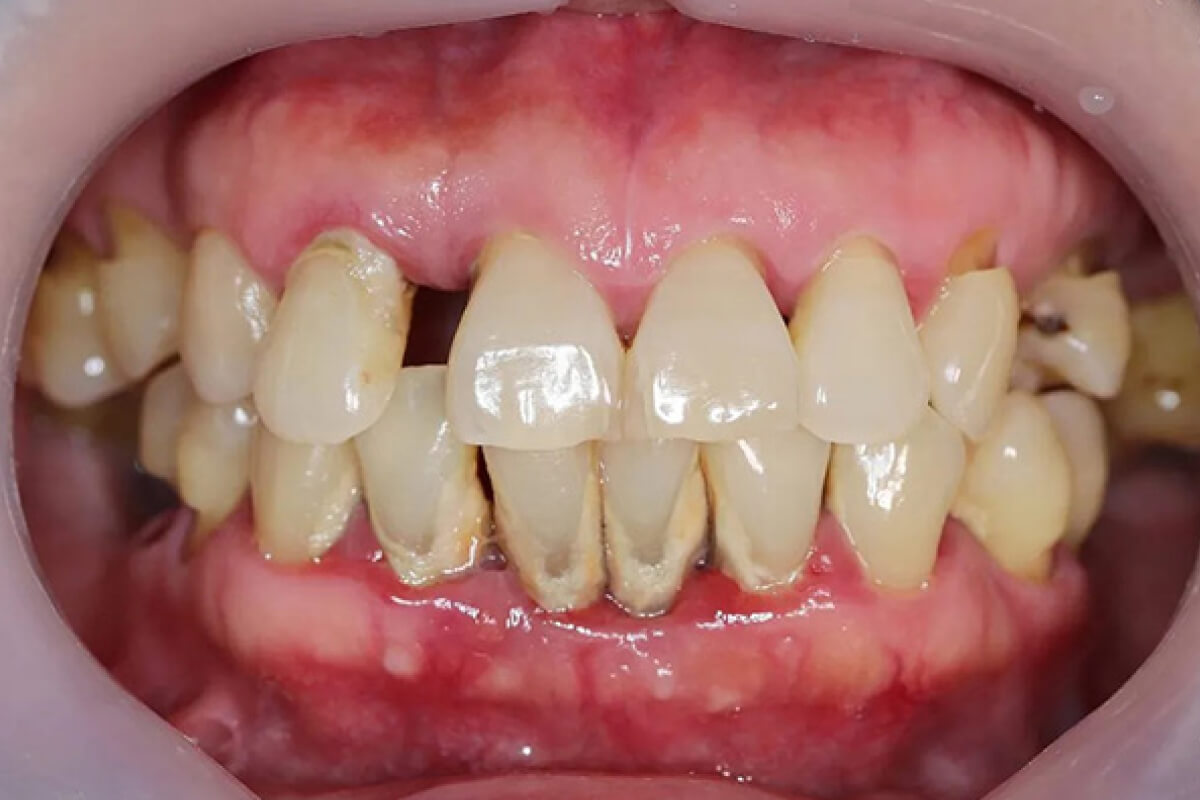

Parodontitída | Dental Centrum NIVY

3. Pokročilé ochorenie ďasien (parodontitída)

Keď zub stratí svoju oporu v kosti a začne sa kývať.